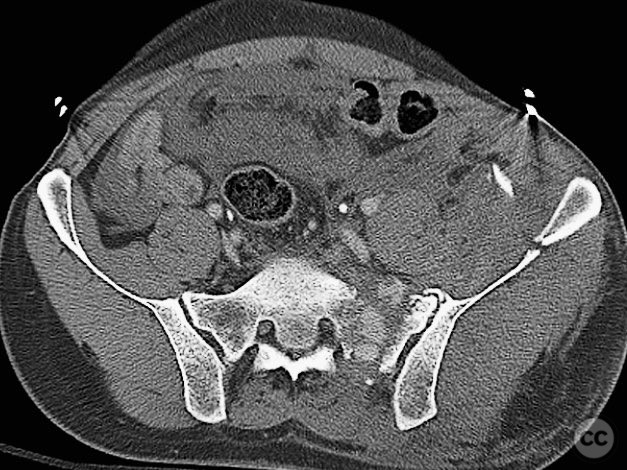

Clinical and radiological findings:  A 42-year-old male sustained a high-energy motor vehicle accident resulting in an unstable pelvic ring injury (AO/OTA 61-C1.3) with hemodynamic instability and associated intraperitoneal bladder rupture. Initial computed tomography demonstrated a complex anterior pelvic ring disruption and a posterior sacral fracture with contrast extravasation and blood within the fracture site. The patient was hemodynamically unstable on presentation.

Planning remarks:  The preoperative plan included multidisciplinary management with urology for bladder repair, followed by open reduction and internal fixation of the anterior pelvic ring via an anterior approach. Subsequent posterior pelvic stabilization was planned after initial resuscitation and anterior fixation, utilizing a posterior approach for direct sacral reduction and percutaneous iliosacral screw fixation.

Anatomical surgical approach:  The anterior approach utilized a Pfannenstiel incision to access the symphysis pubis and pubic rami, with subperiosteal dissection of the rectus abdominis and exposure of the retropubic space for reduction and fixation. For posterior sacral ORIF, a midline longitudinal incision was made over the sacrum, with subperiosteal elevation of the paraspinal musculature to expose the sacral fracture. A tenaculum clamp was applied for direct reduction, followed by percutaneous insertion of iliosacral screws under fluoroscopic guidance.